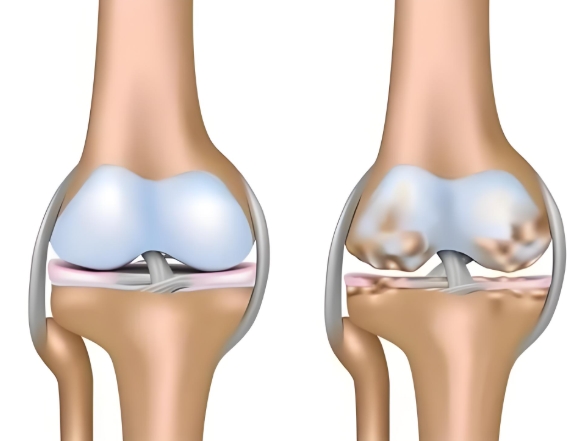

盐酸和硫酸氨基葡萄糖胶囊都是氨基葡萄糖类药物,能为关节软骨提供合成原料,在促进软骨基质的修复与再生的基础上,补充关节滑液以减少摩擦,同时通过抑制关节腔内的炎症因子,从多个方面帮助延缓骨关节炎的进展[1],但它们在临床疗效上却存在一定差异。

根据国际医学四大期刊之一《美国医学会杂志》上发布的一项研究表明,硫酸氨基葡萄糖在缓解膝骨关节炎疼痛、改善关节活动功能方面,效果优于盐酸氨糖等33种骨关节炎常用药[2]。还有相关研究显示,硫酸氨基葡萄糖不仅能延缓关节间隙变窄,还能从根源改善关节结构、减缓磨损。而盐酸氨基葡萄糖在这一关键指标上的效果尚未明确。因此,在关节保护的“确切性”上,硫酸氨基葡萄糖胶囊功效显然更具优势。

硫酸氨基葡萄糖胶囊中含有的硫酸根是人体关节软骨中蛋白聚糖的天然组成成分。这种与人体兼容的“内源性”特质,让它口服后吸收利用率可达90%[3]。而且对胃肠道会更温和,耐受性更佳。反观盐酸氨基葡萄糖胶囊,它所含的氯离子不是关节正常代谢所需,可能会在口服后刺激胃肠道黏膜[4]。这种刺激不仅会引起肠道不适,还会干扰药物在肠道的吸收,降低其生物利用度。